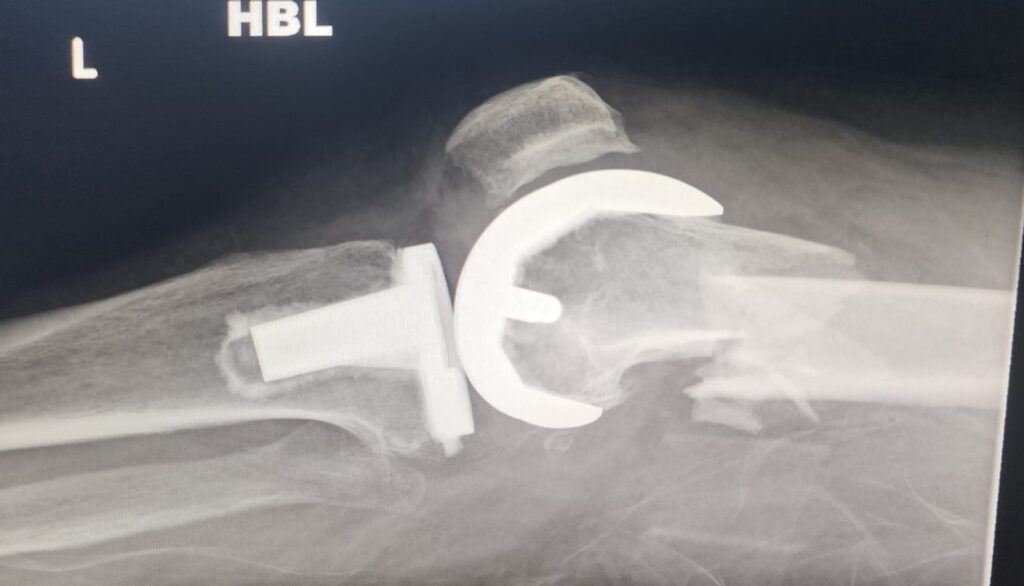

πŸ“Έ X-ray Before Surgery

(Image 1 & 2) – The preoperative radiographs show a clear fracture line around the previously implanted knee prosthesis.

The main concern was maintaining implant stability while achieving fracture union and early mobility.